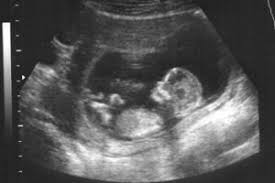

Fibroid rahim, sejenis tumor yang terbentuk di dalam atau pada dinding rahim. Fibroid adalah tumor padat dan padat yang terbuat dari sel otot polos dan jaringan ikat fibrosa. Jadi, apa kesan fibroid dalam rahim? Bulan ni pun sama, baru saja balik bercuti. Rahim adalah organ wanita yang penting.

Fibroid rahim adalah tumor pertumbuhan non kanker di dinding rahim. Pelvik bir sinire baskı yapan bir fibroid, kronik kalça ve sırt ağrısına neden olabilir. Fibroid rahim seringkali membuat wanita cemas karena menyerang rahim. Apa sebenarnya fibroid rahim itu? Fibroid rahim adalah salah satu jenis tumor yang paling banyak terjadi pada wanita. Diperkirakan bahwa antara 20% hingga 50% wanita usia reproduksi memiliki fibroid, meskipun tidak semua terdiagnosis. Perlu kamu tahu bahwa fibroid intramural dapat membesar sehingga dapat meregangkan rahim. Sebagian besar fibroid, bahkan yang besar, tidak menunjukkan gejalanya.

Selengkapnya simak penyebab fibroid rahim hingga pengobatannya. Fibroid rahim kebanyakan berada di dalam rahim. Fibroid rahim adalah tumor pertumbuhan non kanker di dinding rahim. Fibroid rahim adalah tumor bukan kuman yang timbul daripada tisu otot pada rahim. Kesan fibroid yang paling teruk yang boleh menghalang kesuburan wanita. Pada peringkat pertama, rawatan fibroid adalah lebih mudah daripada dalam kes penyakit yang di hadapan fibroid rahim agak berkesan. Pembedahan yang membuang fibroid atau rahim yang melampau boleh dilakukan, tetapi ramai wanita memilih untuk merawat keadaan mereka dengan kaedah semula jadi, termasuk menonton makanan yang dimakan. Sebagian besar fibroid, bahkan yang besar, tidak menunjukkan gejalanya. Fibroid intramural adalah tipe fibroid rahim yang paling umum. Muhammad izzat, seorang pegawai perubatan kesihatan wanita & kehamilan, di laman facebook beliau dan pihak iluminasi mendapat kebenaran untuk mengulang siar penulisan ini untuk manfaat bersama. Perlu kamu tahu bahwa fibroid intramural dapat membesar sehingga dapat meregangkan rahim. Fibroid atau leiomyomata adalah ketumbuhan abnormal yang membesar dalam rahim. Fibroid adalah ketumbuhan benigna dinding rahim.

Apakah fibroid rahim pada wanita? Fibroid rahim seringkali membuat wanita cemas karena menyerang rahim. Selengkapnya simak penyebab fibroid rahim hingga pengobatannya. Fibroid intramural adalah tipe fibroid rahim yang paling umum. Fibroid dapat meningkatkan komplikasi kehamilan dan risiko saat melahirkan.